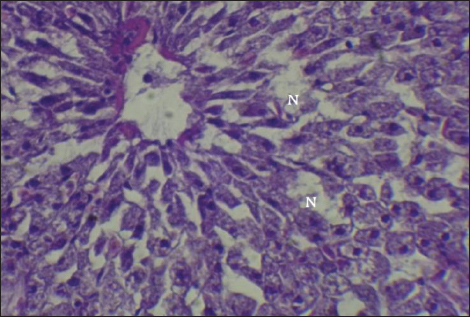

The result of histopathological alteration of the liver revealed degenerative and necrotic changes in liver tissue distinguished by pyknosis with the existence of necrosis in cells (Figs. 14 and 15) also, the result revealed dilation of the sinusoids with cytoplasmic vacuolation (Fig. 16).

Fig. 14. Histopathological sections of liver of C. carpio showing necrosis(N) and Pyknosis (P) (H&E X40).

This study showed that C. carpio contains different concentrations of the selected heavy metals in the liver, gill, and muscle, the causes of this differences is due to the collection of samples at different intervals and, therefore, the level of contamination in water and food and sediment varies depending on the time period also differences in fish’s internal uptake and water temperature. Kalay et al. (1999) revealed that the amounts of minerals that different fish species accumulate in their tissues vary noticeably. Furthermore, Canli and Atli (2003) revealed that heavy metals levels in fish vary between species and different aquatic environments. Conversely, Farkas et al. (2000) linked variations in mineral concentrations among fish to their feeding habits, the ability of each species to bioconcentrate, and the mineral’s biochemical characteristics. Roméo et al. (1999) also state that the environment, metabolism, needs, level of contamination in water, sediment, and food, as well as water temperature and salinity, all affect a fish’s ability to accumulate heavy metals. Also, Brraich and Kaur (2017) revealed that the levels of heavy metals in different fish organs are directly impacted by the contaminating of the aquatic environment and by the fish’s internal uptake, control, and removal of heavy metals.

It is well known that exposure to heavy metals can cause a variety of histopathological changes (Mustafa et al., 2012). These changes may be related to the harmful effects of heavy metals on hepatocytes, as the liver is involved in the biotransformation and detoxification of various pollutants and toxicants (Arellano et al., 1999). The observed necrosis in certain areas of the liver tissue may have been caused by the fish’s overwork in eliminating the toxins from its body during the detoxification process; this observation is consistent with the findings of Rhaman et al. (2002).